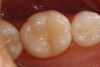

The tooth was then restored with a flowable composite (Premise™ Flowable, Kerr Corporation, www.kerrdental.com). Care must be taken in the choice of a flowable composite as a restorative material. CRA listed flowable composite as a restorative material option for a Class I restoration,15 yet in 2003 Dr. Christensen stated that care should be taken when issues of occlusal wear may be a concern.16 Flowable composites are basically watered down conventional composites with less filler particles; therefore, they will be less wear resistant. Care and caution should be used when deciding to use a flowable composite as a restorative material for a Class I or II restoration.16

In the clinical case shown, the occlusal contacts were checked before the preparation was started. It was determined that there would be no occlusal contacts in the areas to be prepared, so the restorative flowable material would not be subject to direct occlusal wear. The very narrow and slightly deep nature of the preparation and the absence of occlusal contacts create a situation that is well suited for a flowable composite. Flowable composite, because of its viscosity, allows for it to easily flow and adapt to the narrow preparation, ensuring an absence of voids and excellent adaptation to the preparation. When properly placed, finishing should be minimal.

Figure 3 shows the final conservative, esthetic restoration.

Figure 3  The final Class I restoration was created using a flowable composite.

Figure 3